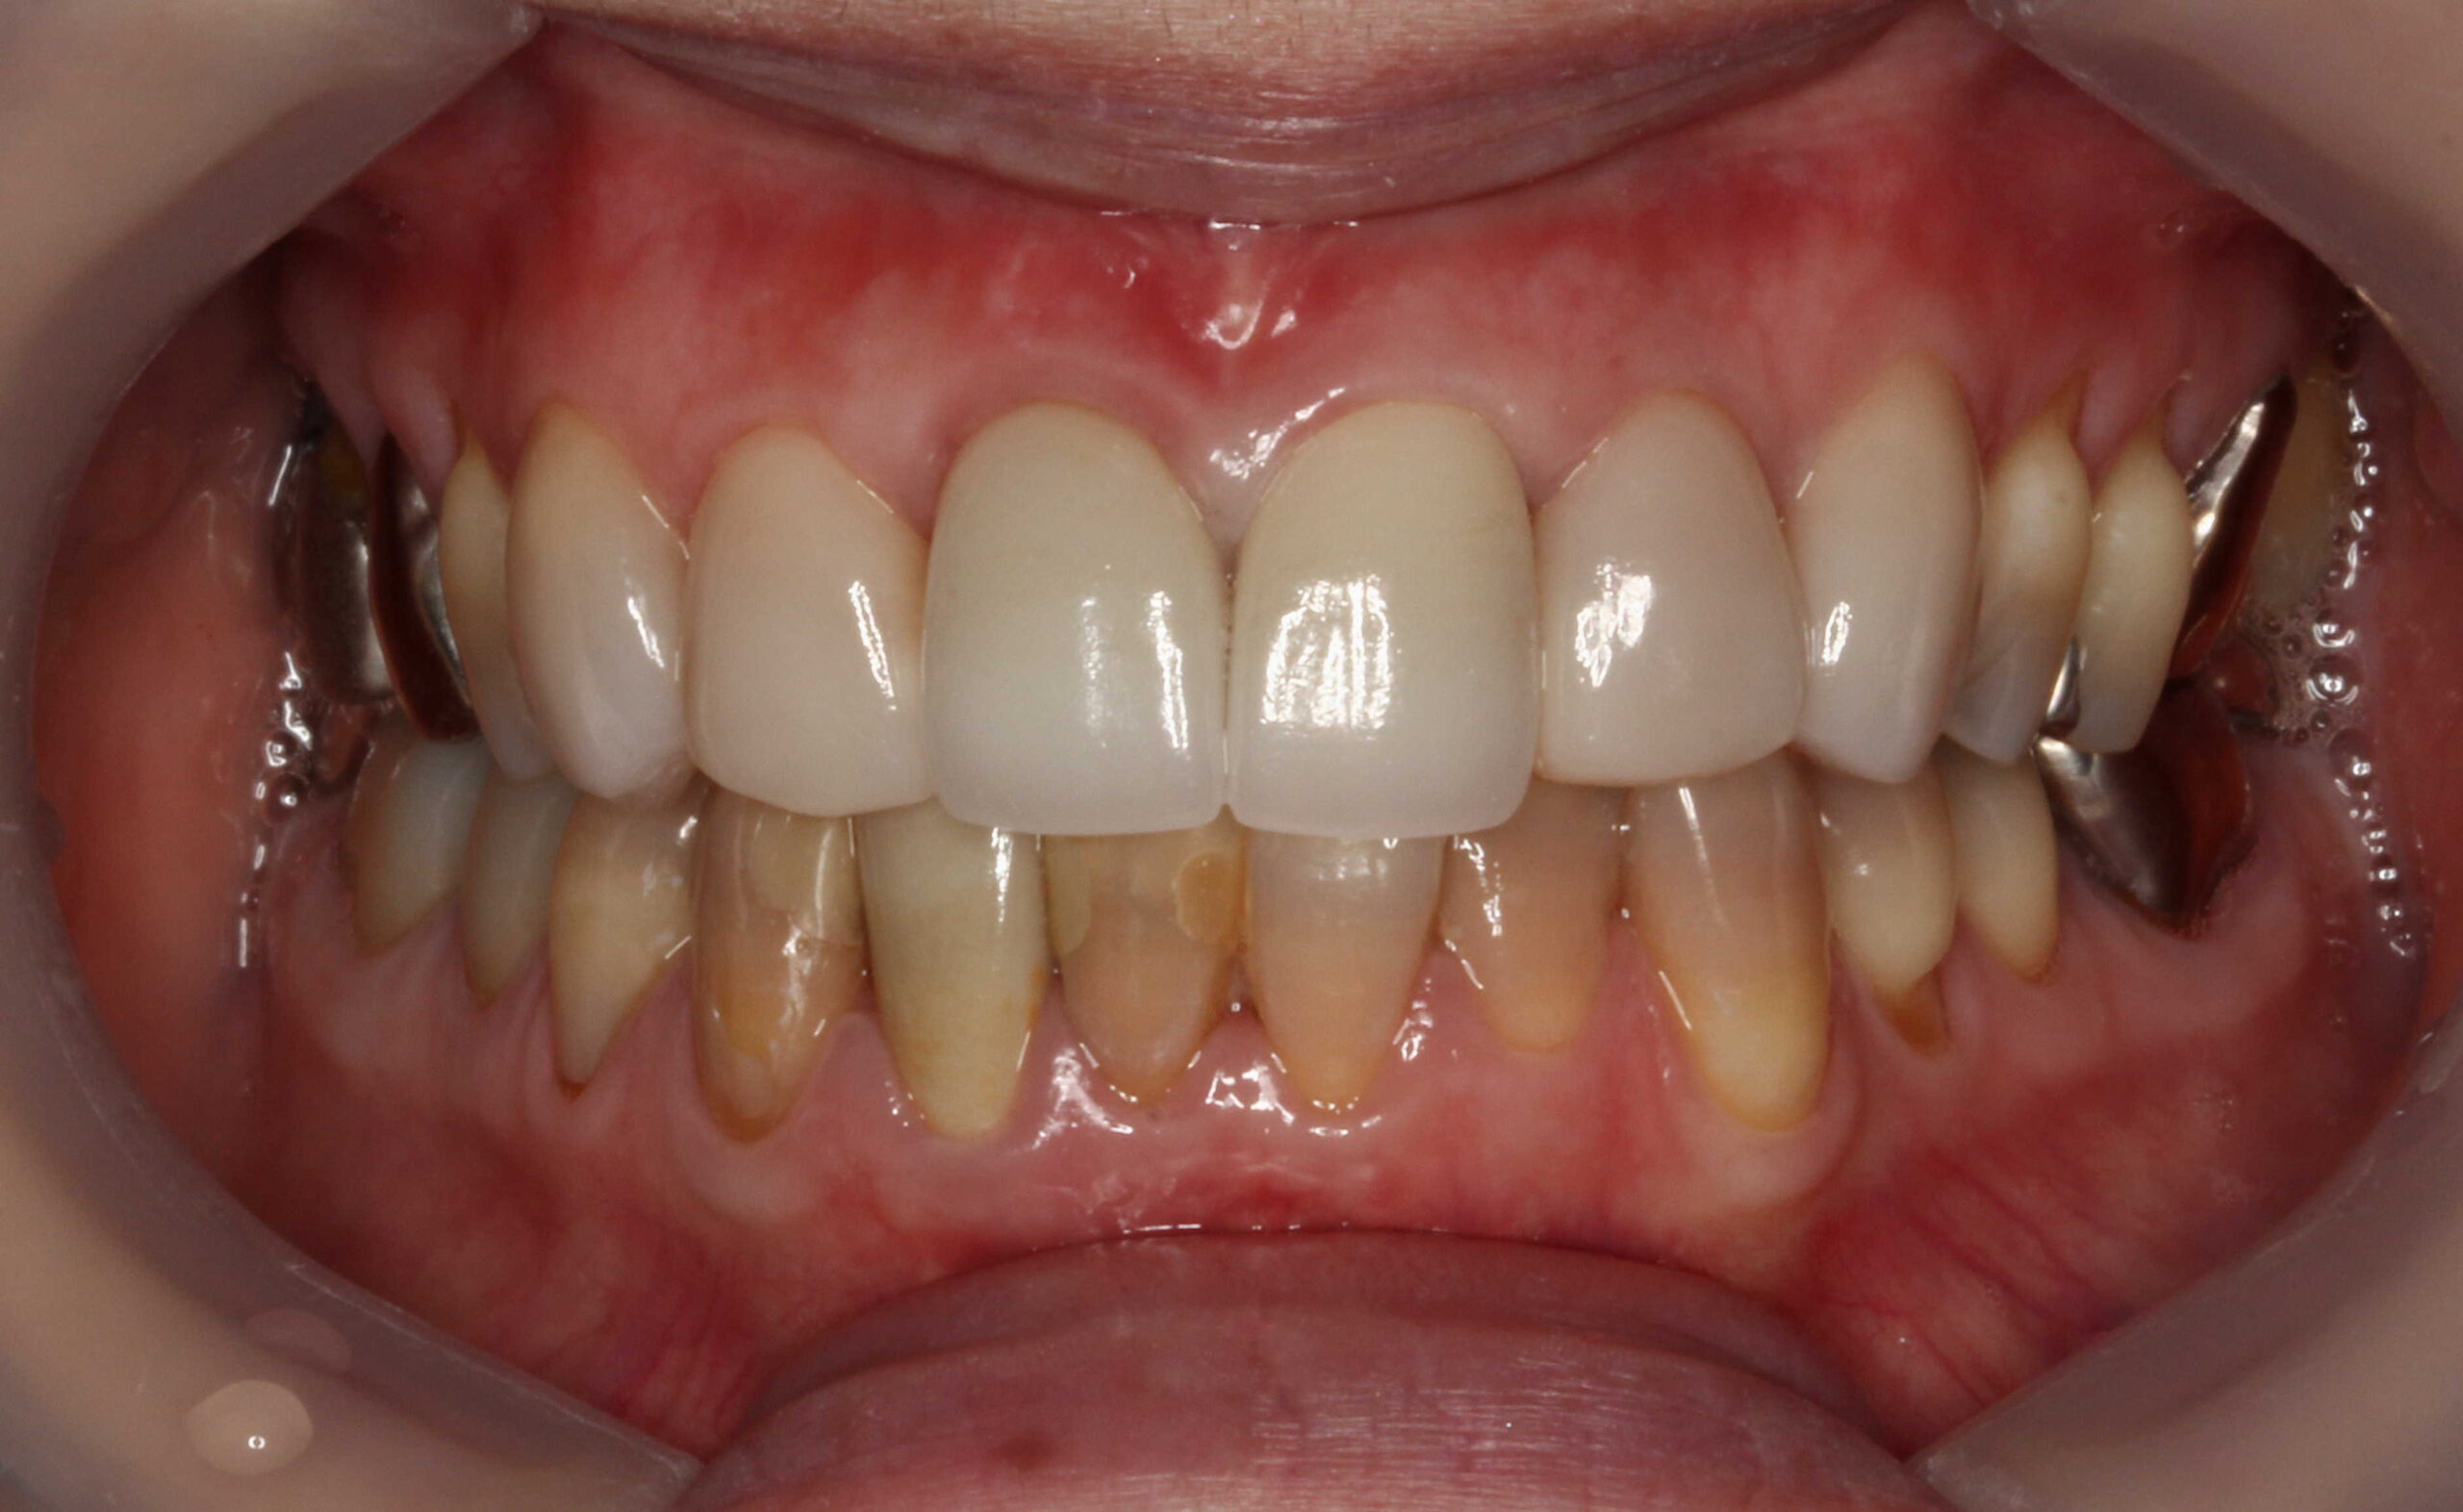

テトラサイクリン歯と失活歯と古いクラウンの症例

こちら、テトラサイクリン歯と失活歯と古いクラウンの症例となっております。

術前 削らないラミネートベニア4本

+クラウン2本

全体的にはホワイトニングを行っています。

テトラサイクリン歯 と 左上2や右下1などの失活歯 にもホワイトニング効果は出ています。

削らないラミネートベニアは極薄のセラミックベニアなので透明感があるので元の歯の色味が透けます。(透過性のないベニアも製作出来ますが、透明感がないので色味が白浮きして不自然になります。)

上の前歯(右上32と左上23) にも、削らないラミネートベニアの前にホワイトニングを行っています。

従来の方法であれば、上前歯6本をラミネートベニアやセラミッククラウンを行うために削って、セラミック材料を被せる方法で行っていました。